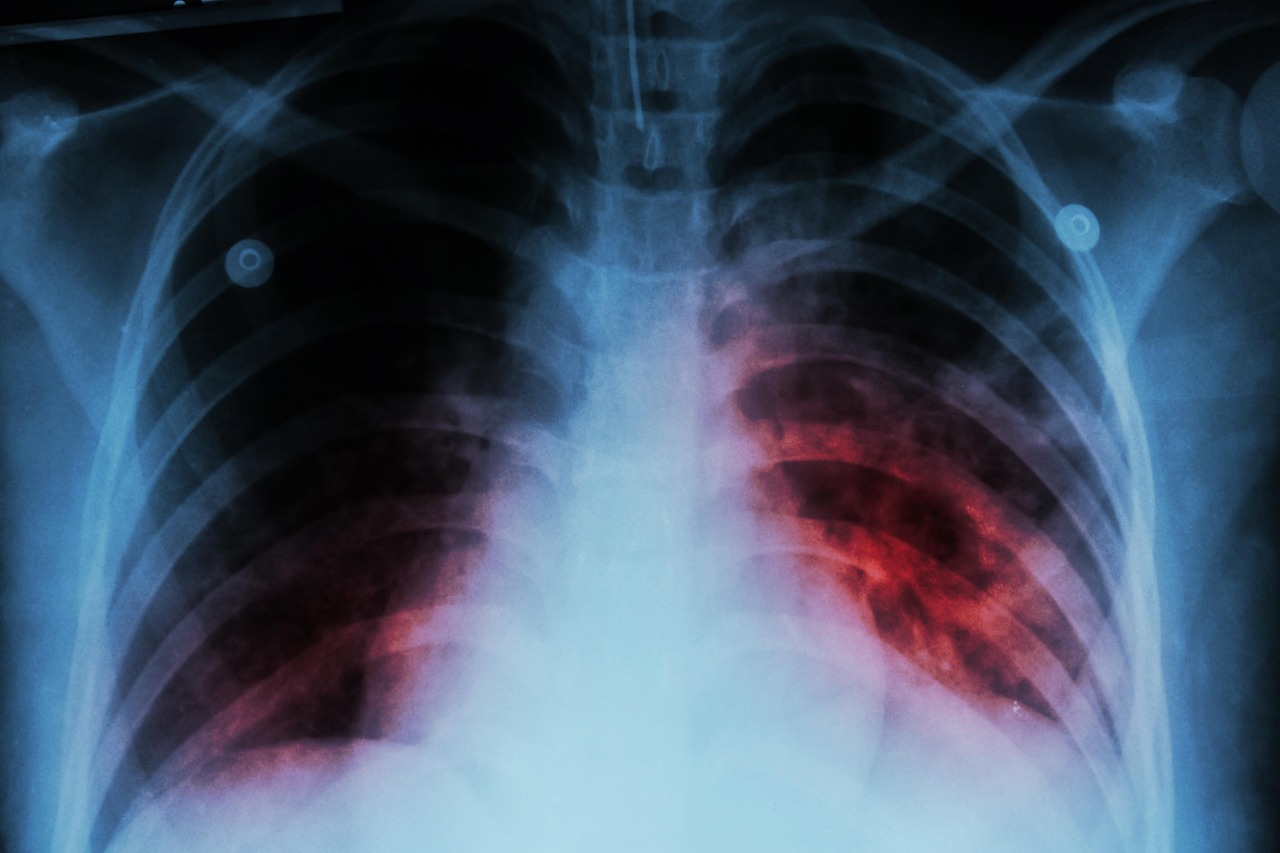

Es preocupante la cantidad de enfermos de tuberculosis activos que en este momento se encuentran detectados en la región de Puerto Vallarta, al llegara en este momento a 203 contagiados.

Lo anterior fue señalado por Jaime Álvarez Zayas, director de la VIII Región Sanitaria, al indicar que la tuberculosis es una enfermedad que se consideraba que ya no había generado contagios; sin embargo, a últimas fechas hay una buena cantidad de infectados.

“La atención especializada por lo que ya mencionamos al principio está laboratorio de Salud Pública donde precisamente en pacientes para tuberculosis de exámenes se hicieron mil 660 baciloscopias positivas y 206 negativas en un gran problema de tuberculosis, eso tampoco no hablamos mucho. Tenemos el día 24 de marzo el Día Mundial tuberculosis y precisamente tenemos este problema salud pública, ahorita tenemos activos 203 casos de tuberculosis, porque pensamos que esa enfermedad no existe no se habla socialmente, por supuesto”.

El médico de profesión indicó que dichos enfermos están siendo atendidos en diferentes clínicas y hospitales del sector público como son la SSJ con 109 enfermos, el IMSS con 89 contagiados, el ISSSTE atiende a cuatro personas y en el Hospital Naval Militar se atiende un enfermo.